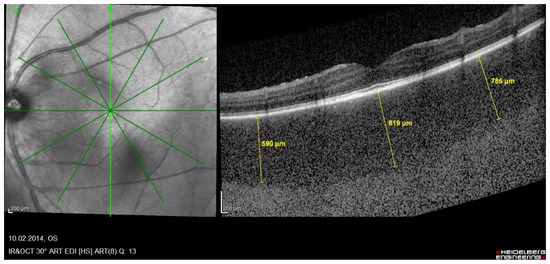

Choroidal Enhanced-Depth Imaging OCT (EDI-OCT)

- Skvortsova, N.; Gasc, A.; Jeannin, B.; Herbort, C.P. Evolution of choroidal thickness over time and effect of early and sustained therapy in birdshot retinochoroiditis. Eye 2017, 31, 1205–1211. [Google Scholar] [CrossRef] [PubMed][Green Version]

- Silpa-Archa, S.; Maleki, A.; Roohipoor, R.; Preble, J.M.; Foster, C.S. Analysis Of Three-Dimensional Choroidal Volume with Enhanced Depth Imaging Findings in Patients with Birdshot Retinochoroidopathy. Retina 2016, 36, 1758–1766. [Google Scholar] [CrossRef] [PubMed]

- Balci, O.; Gasc, A.; Jeannin, B.C.P.H., Jr. Enhanced depth imaging is less suited than indocyanine green angiography for close monitoring of primary stromal choroiditis: A pilot report. Int. Ophthalmol. 2016, 37, 737–748. [Google Scholar] [CrossRef]